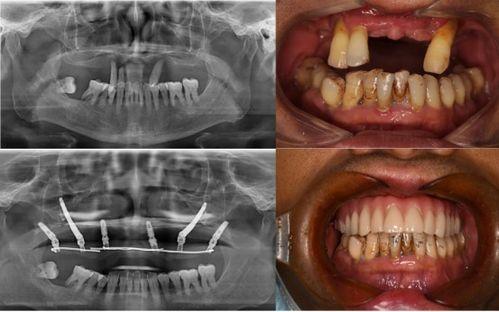

在舆论的压力下,当地卫生部门迅速介入调查。经过一番调查,发现这家口腔医院在种植牙过程中存在诸多违规操作。比如,医院使用的种植体并非正规厂家生产,而是通过非法渠道购入的假冒伪劣产品。此外,医院在手术过程中,还存在操作不规范、消毒不严格等问题。

在调查结果公布后,这家口腔医院不得不向患者和小李道歉。医院表示,将立即停止使用假冒伪劣产品,并对患者进行赔偿。同时,医院还承诺将进行全面整改,加强内部管理,确保医疗质量和安全。